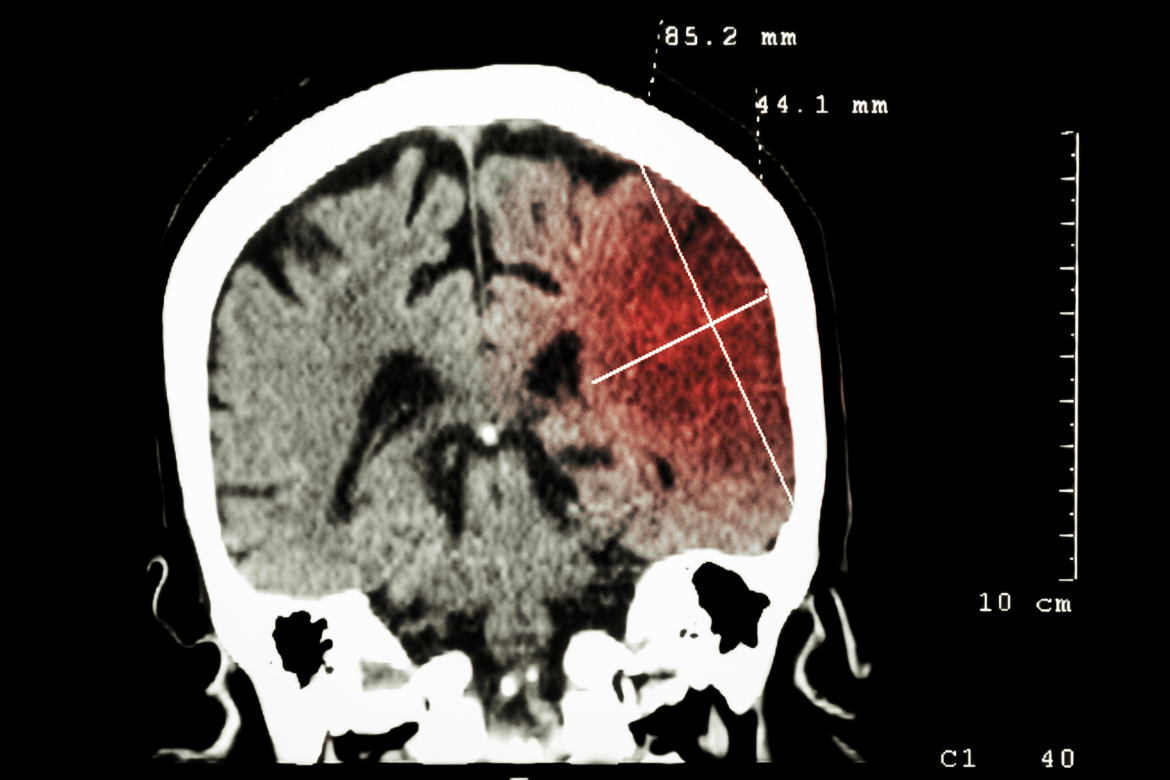

En primer lugar, un infarto cerebral, también conocido como accidente cerebrovascular isquémico, ocurre cuando una parte del cerebro no recibe suficiente oxígeno debido a la interrupción del flujo sanguíneo. Esto puede suceder por el bloqueo de una arteria cerebral, generalmente debido a la acumulación de placas (colesterol o grasas) en los vasos sanguíneos, lo que se conoce como aterosclerosis.

El infarto cerebral causa que el tejido del cerebro en la zona afectada comience a morir, lo que puede provocar secuelas permanentes, dependiendo de qué tan grande sea el área afectada y cuán rápido se reciba tratamiento.

Por otro lado, la embolia cerebral es un tipo específico de accidente cerebrovascular isquémico que ocurre cuando un coágulo de sangre, una burbuja de aire, o una partícula de grasa (embolia) viaja a través del torrente sanguíneo y llega a una arteria en el cerebro, bloqueando el flujo de sangre. Esto puede provocar un daño similar al de un infarto cerebral.